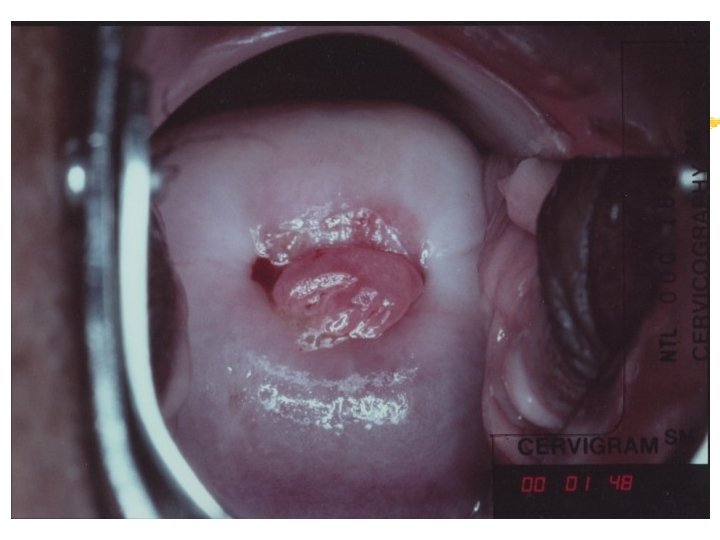

HPV infection Condyloma Accuminata Exophytic Frond like surface Lesion may be single or multiple Located within or outside the transformation zone

Cervicography: This is NOT Colposcopy High-quality colposcopic-type photography of the cervix Cervicoscope - Hand-held camera with a macrolens and a ring-flash Cervicogram - 35 -mm photo slide is taken Principles Recognition of lesions by means suitable magnification and illumination Fix up the problems of colposcopy 1. a less expensive form 2. noninvasive method 3. do not require expert skill

Procedures of cervicography A) Taking a 35 -mm cervicogram (1) Insert speculum and open as wide as possible … expose an entire cervix and upper vagina (2) Apply first application of 5% acetic acid by dabbing … cleanse the cervix of blood and mucus (3) View the cervix through the cervicoscope … allows time to begin taking epithelial change (4) Apply second application of acetic acid. (5) Take two cervicogram pictures B) Developing the images C) Interpreting a magnified image that was projected on the screen (1) Negative if no definitive lesions are visible (2) Atypical if there was evidence of acetowhite lesion of doubtful significance (3) Positive if there was evidence of a minor or major-grade lesion or cancer